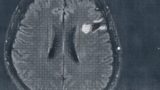

簡単に自分の病気の説明をしておくと、グリオーマ(【備忘録】グリオーマ・びまん性星細胞腫:神経膠腫)という脳の実の部分にできる悪性腫瘍です。グレード1~4で悪性度を表すのですが、グレード2の判定です。

非常に幸運なことに無症状の段階で発見できたので、悪性度はまだ低くてサイズも小さいです。それでもピンポン球くらいあります。

腫瘍が言語中枢の近くにありデリケートな手術となりますので、地元の病院で紹介してもらった大学病院で手術します。